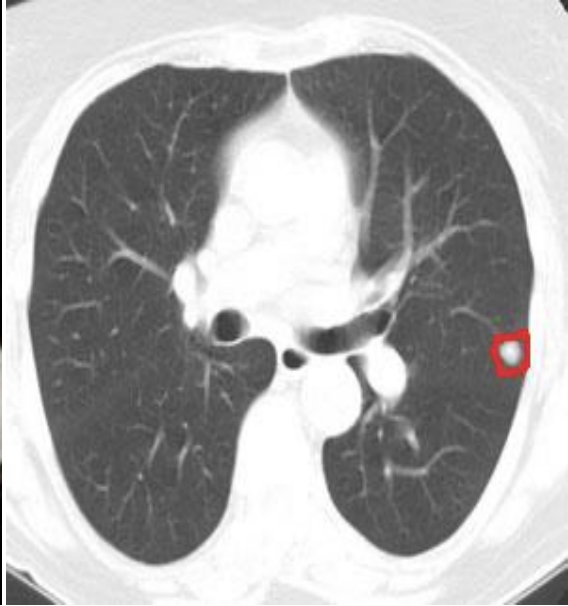

Fed-LIDC-IDRI.

LIDC-IDRI [armato2011lidc, lidcdata, clark2013cancer] is an image database [clark2013cancer] study with 1018 CT-scans (3D images) from The Cancer Imaging Archive (TCIA), proposed in the LUNA16 competition [setio2017validation]. The task consists in automatically segmenting lung nodules in CT-scans, as measured by the DICE score [dice1945measures]. It is challenging because lung nodules are small, blurry, and hard to detect. By parsing the metadata of the CT-scans from the provided annotations, we recover the manufacturer of each scanning machine used, which we use as a proxy for a client. We therefore build a 4-client federated version of this dataset, split by manufacturer. Figure 1(b) displays the distribution of voxel intensities in each client.

As a baseline model, we use a VNet [milletari2016v] following the implementation from [adaloglou2019MRIsegmentation]. This model is trained by sampling 3D-volumes into 3D patches fitting in GPU memory. Details of the sampling procedure are available in Appendix D.

Appendix D Fed-LIDC-IDRI

D.1 Description

LIDC-IDRI [armato2011lidc, lidcdata, clark2013cancer] is part of The Cancer Imaging Archive (TCIA) database [clark2013cancer] with 1009 lung CT-scans (3D images), on which radiologists annotated the presence of nodules.

We split the dataset in 4 different clients that correspond to different medical imagery machine manufacturers, which were previously shown to be a source of heterogeneity in CT image quality [favazza2015cross]. We end up with 661 samples gathered by GE Medical Systems, 205 by Siemens, 69 by Toshiba, and 74 by Philips scanner. These datasets are further split in training and testing sets that contain respectively 80% and 20% of the data. This split is stratified according to clients, so that proportions are respected. The exact distribution of the samples between clients are given in Table 3

D.3.1 Preprocessing and sampling

Raw CT scans have varying dimensions which must be standardized prior to training. Therefore, as a first step we resize them to a common (384,384,384)384384384(384,384,384) shape by cropping dimensions in excess and reflection-padding missing dimensions. During training, this operation is performed in the same way both on the CT scans and the ground truth masks.

Next, the images are normalized. CT scan voxels are originally expressed in the Hounsfield unit (HU) [feeman2010mathematics] scale: roughly 1,0001000-1,000 HU for air, 00 HU for water, and 1,00010001,000 HU for bone. We clip the images to the [1024,600]1024600[-1024,600] range, add 102410241024, and then divide voxels by 162416241624 to obtain values ranging in [0,1]01[0,1].

D.4 Task

We benchmark federated learning strategies on a nodule segmentation task using a VNet [milletari2016v]. More precisely, we aim to maximize the DICE coefficient [dice1945measures] between predictions and the annotated ground truths. For reference, the baseline model trained on the pooled training set achieves a DICE of 41%percent4141\% on the pooled test set.